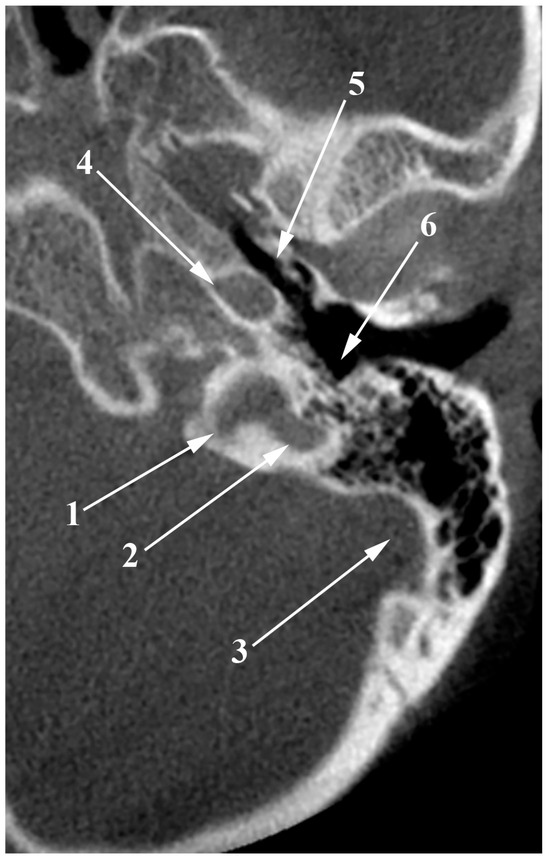

4. High Jugular Bulb

5. Dehiscent Jugular Bulb